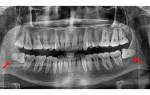

Когда зуб мудрости вызывает постоянную боль, необходимо обратиться к стоматологу и сделать рентгенограмму. Стоматолог проведет осмотр и санацию зуба мудрости. Вопрос о том, лечить или удалять, является сложным и решается совместно пациентом и врачом. Рентгеновский снимок позволит получить наглядное представление о расположении верхушки и корней в челюсти и определить возможность лечения. Выбор между «лечить или вырвать» зависит от того, насколько целесообразно сохранять и лечить зуб мудрости.

Удаление зуба мудрости сложнее, чем других многокорневых моляров, по двум причинам. Во-первых, эти моляры находятся в самом крайнем положении и наиболее удалены от центра, поэтому для проведения операции пациенту необходимо широко открывать рот. Во-вторых, корни этих моляров изогнуты и могут иметь значительные изгибы, похожие на крючки, что делает удаление еще более сложным.